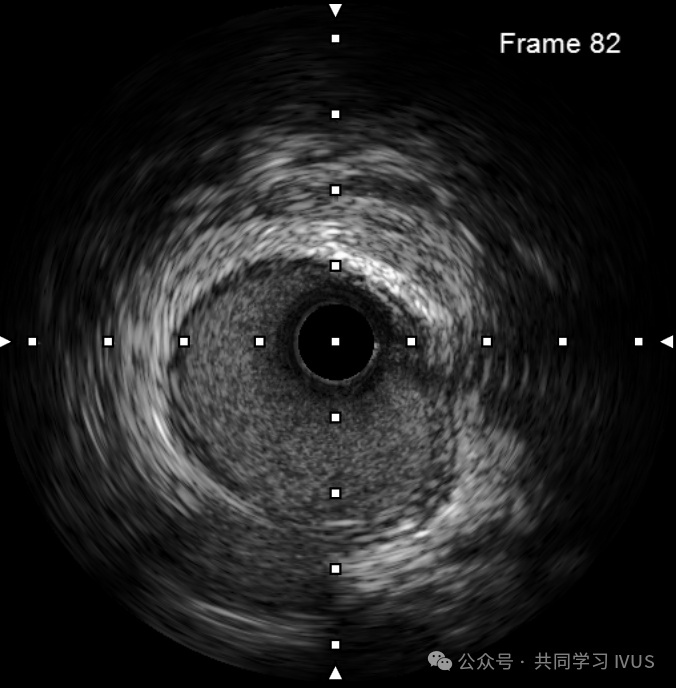

正常血管结构:可见导管在血管内,可见三层膜结构,管腔内可见黑色或黑白相间的“闪烁”血流信

1、回波密集的血管内膜层

2、无回波层:血管中膜层:平滑肌细胞

3、血管外膜层:回波密集:弹性蛋白和胶原蛋白:纤维化

4、盲区:超声导管

5、超声导管伪影“光晕”

6、管腔:血液

7、导引导丝伪影